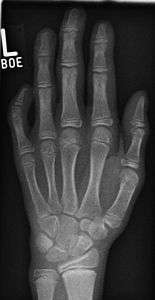

| The picture above illustrates a moderately severe case of this condition. | |

Radiograph showing clinodactyly